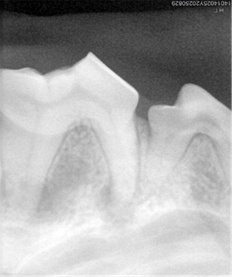

接诊的姜医生检查后发现,肉肉的上颌第四前臼齿严重齿折。因长期啃咬硬骨头,加上某次玩耍用力过猛,牙齿断裂后未及时处理,导致牙髓暴露感染,脓液蔓延至眼眶下方,形成了触目惊心的肿包。

姜医生迅速制定方案:鉴于感染已扩散,微创拔牙是根除感染源的最佳选择。